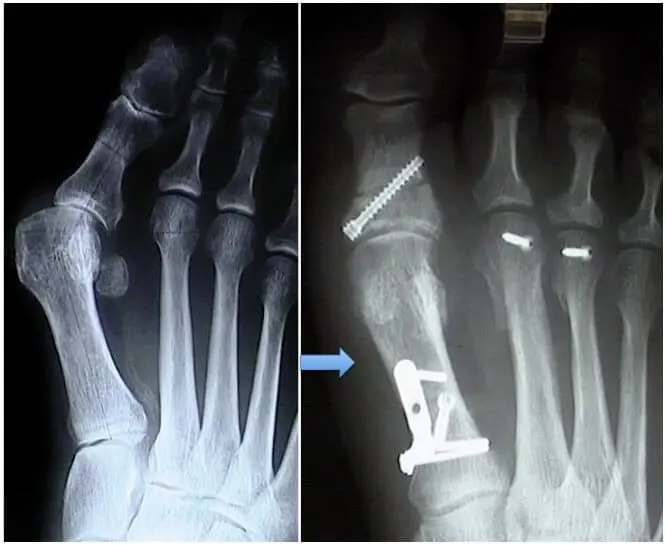

Une ostéotomie: Selon la gravité de la déformation et de l’orientation des surfaces articulaires, l’ostéotomie peut être pratiquée à la base (basale ou proximale), au centre du métatarsien (diaphysaire) ou à son extrémité (distale).

Des ostéotomies distales, comme le Chevron et le Scarf, sont des reconstructions auto- stables fixées à l’aide d’une vis qui restera en place.

Souvent, cette correction bénéficie également d’une ostéotomie de la première phalange (Akin).

La remise en tension des capsules articulaires